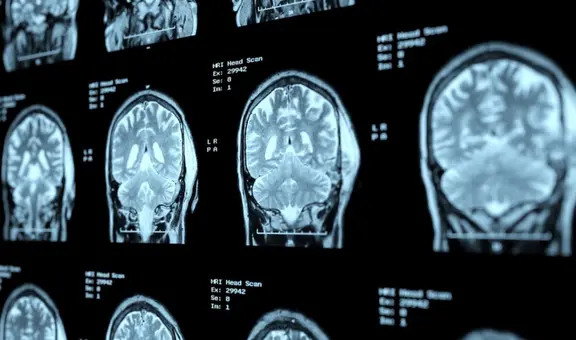

Tau es una proteína que contribuye al correcto funcionamiento de las neuronas y el cerebro. Su principal función es mantener la estructura microtubular, la cual permite el movimiento de los axones de las neuronas y facilita la transmisión de información.

Sin embargo, con el pasar de los años, estas proteínas pueden presentar fallas. La formación de ovillos neurofibiliares de Tau son uno de los principales biomarcadores de indicios de alzheimer, según un artículo publicado en la Biblioteca Nacional de Medicina de los Estados Unidos. Así, las redes neuronales dejan de funcionar adecuadamente.